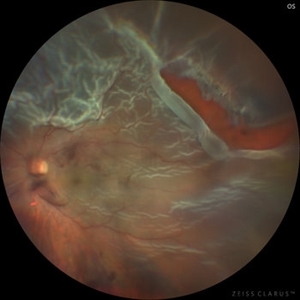

Chronic Open Funnel Retinal Detachment With Horse Shoe Tear

Feb 7 2024 by Harsh Vardhan Singh, MS

67 year old male with history of cataract surgery 1 year presented with old chronic retinal detachment with open funnel configuration with multiple breaks.

Photographer: Harsh Vardhan Singh

Imaging device: Clarus 700

Condition/keywords: chronic retinal detachment, Retinal Detachment, Retinal Detachment with multiple breaks